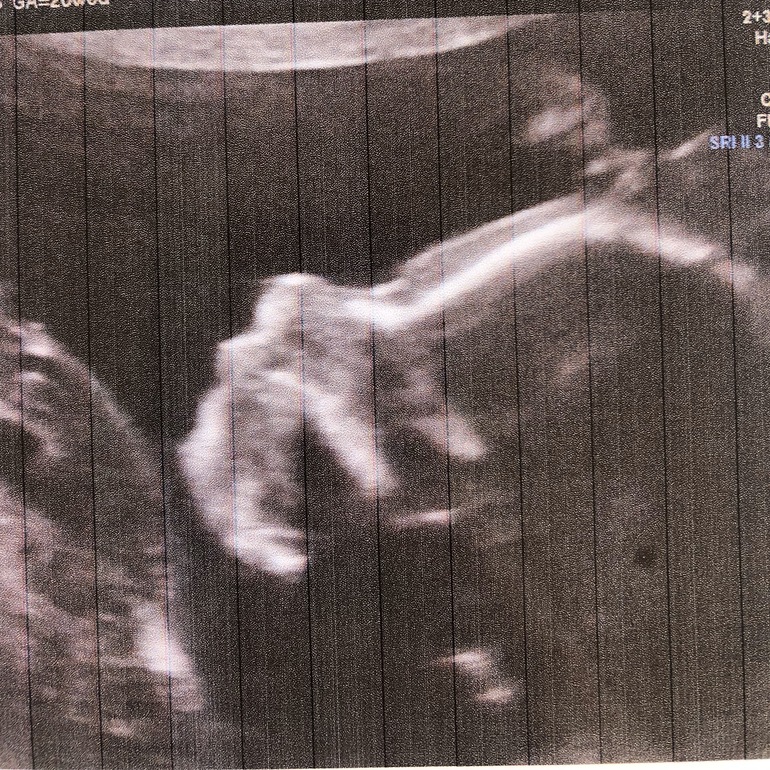

Вопросы про УЗИ, обследования и анализы: что, где, как, когда?Ну вот снова мое узи .все в норме , кроме шейного отека который 7.1 .. сказали , что отёк увеличился, потому что плод вырос .. сегодня 28.3 и вес наш 1.350... nasal bone наш 7.6 , что по российским меркам мало, а тут в норме . Насчёт носа беспокойств мало , так как у самой нос короткий , а вот шея беспокоит ( как не сойти с ума до родов ( делать тест на генетические отклонения отказалась на 100 пр, смысла не вижу ... если все подтвердится будет тяжело донашивать , а так приму как факт .. да ещё есть Надежда , врач ее вселяет говоря, что может быть вариант нормы. Попросила фотку профиля, узист сказал , на вид все в норме, а вот мне смущает сглаженный лоб ... может положение такое у плода , не знаю , что думать .... фото под катом